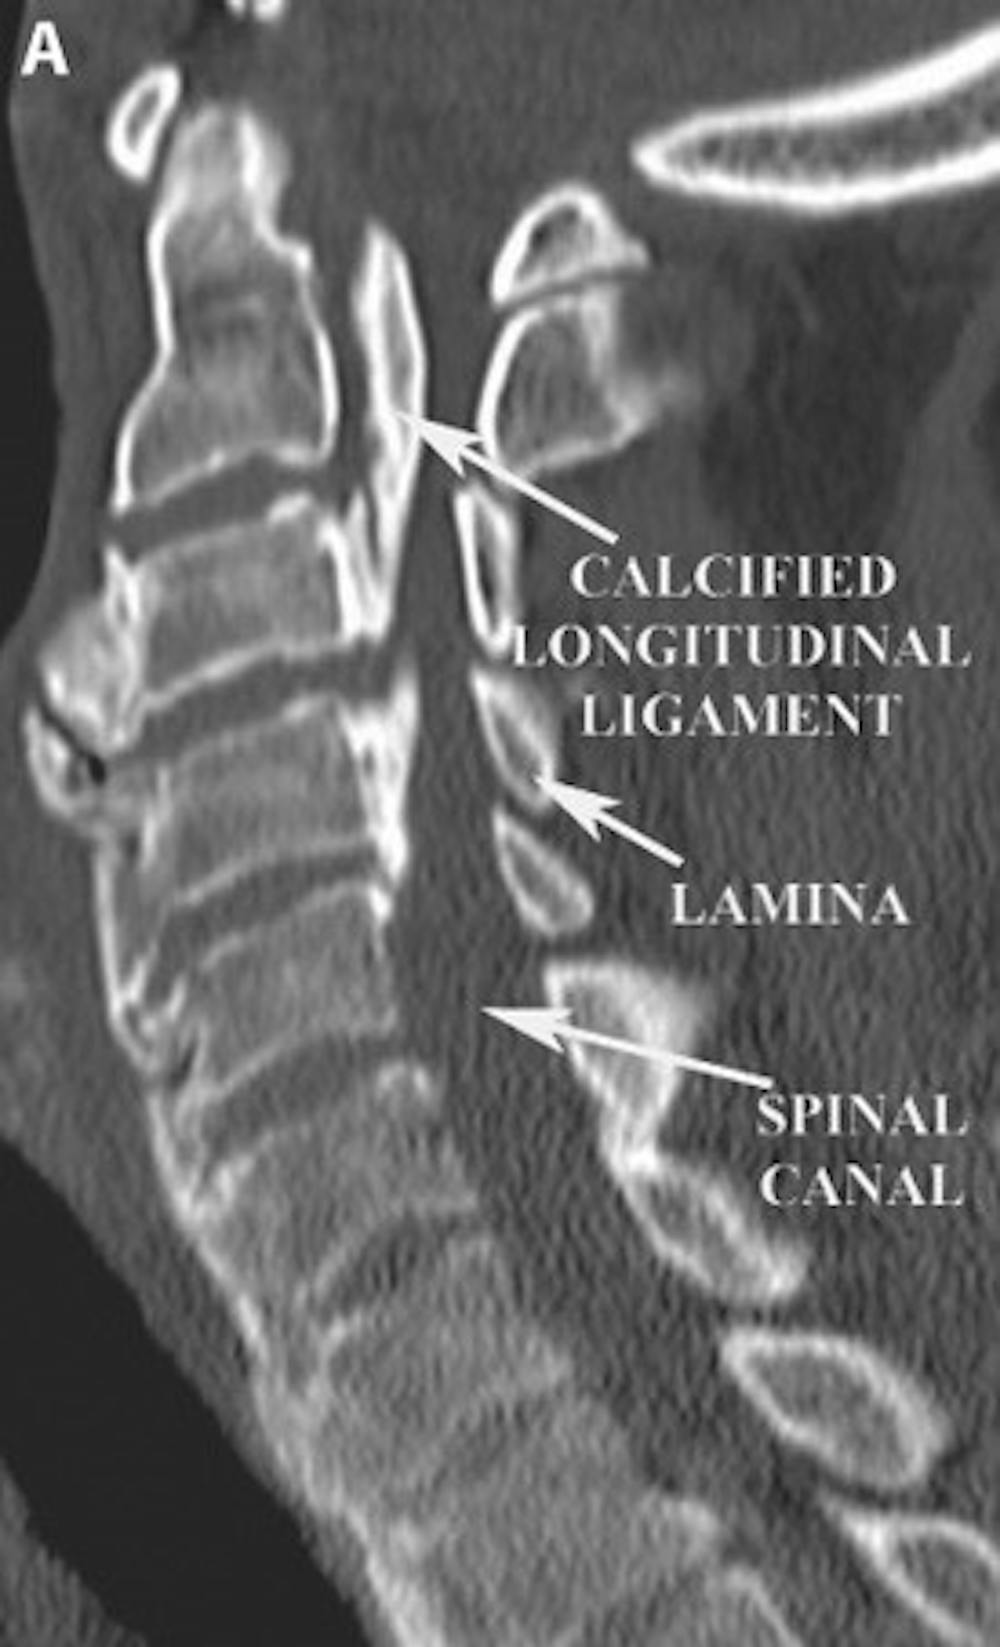

A) 頸椎矢狀 CT 掃描顯示由於後縱韌帶鈣化導致椎管嚴重狹窄。請注意,構成椎管後部的骨骼稱為椎板。